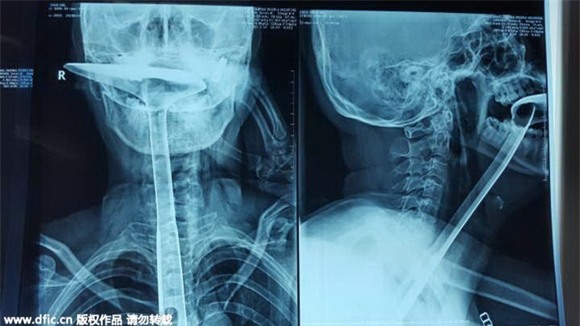

Người phụ nữ ban đầu đã cố gắng dùng ngón tay để 'móc họng', tiếp theo là dùng đũa, nhưng tất cả đều không có hiệu lực. Cuối cùng, cô đặt một thìa kim loại trực tiếp vào miệng và thông nó sâu xuống thực quản. Chiếc thìa sắt dài khoảng 30cm.

Rất may, sự việc đã được con gái của người phụ nữ này phát hiện và đưa đến bệnh viện cấp cứu.